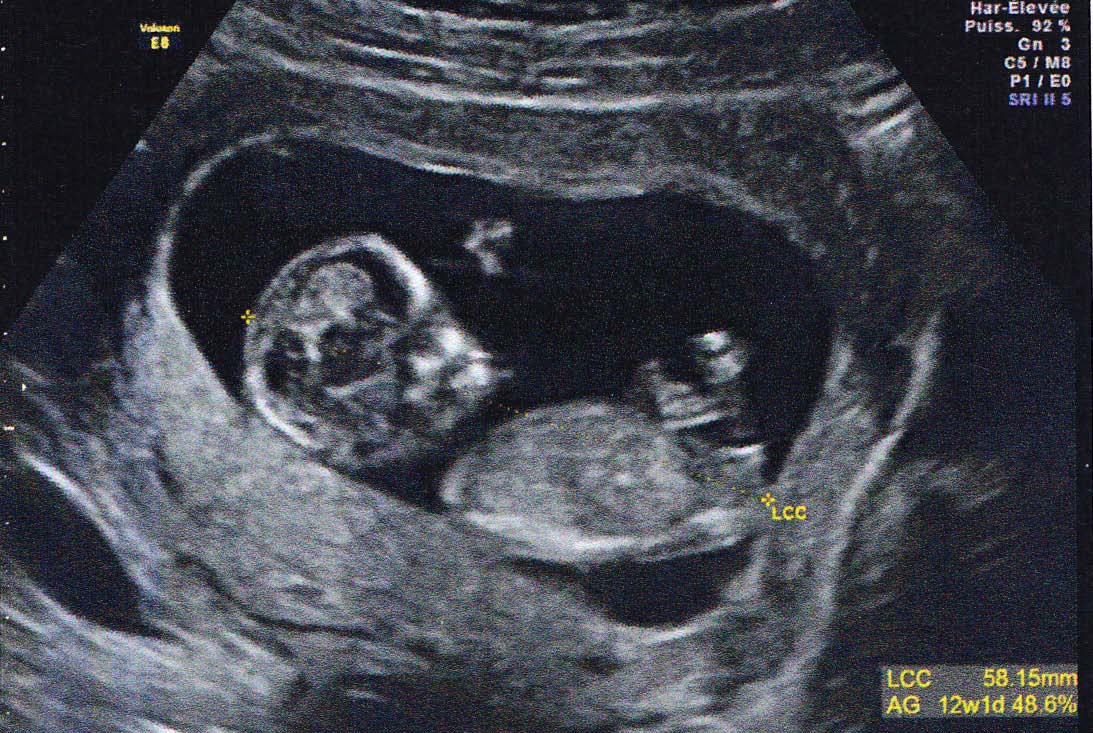

A 14 SA (semaines d'aménorrhée), soit 12 semaines de grossesse effective, c'est bientôt la fin de votre troisième mois de grossesse Votre corps continue de changer, notamment la poitrine et surtout le ventre qui s'arrondit Bébé poursuit quant à lui sa croissance, ses organes sont désormais opérationnels C'est aussi le moment d'envoyer votre déclaration de grossesse Tableau de biométrie foetale DISTANCE CRANIO CAUDALE (TETE FESSES ) EN MILLIMETRES à 5 semaines d'aménorrhée 1 à 2 mm à 7 semaines d'aménorrhée 8 mm à 9 semaines d'aménorrhée 25 mm à 10 semaines d'aménorrhée 33 mm à 11 semaines d'aménorrhée 43 mm à 12 semaines d'aménorrhée 55 mm à 13 semaines d'aménorrhée 68 mm à 14 Votre commentaire date un peu mais je suis dans la même situation que vous a l inverse j ai 3 garcons et 1 fille et je suis enceinte de mon 5ème bébédepuis lapremiere écho la gynéco m a dit que c était encore un garconje suis à 22 sa je vais avoirmon écho morpho la semaine prochaine mais depuis 12 sa je suis déçue de savoir

On la mesure lors du premier trimestre (jusqu'à 14 SA) Elle est de 55 mm en moyenne à 12 SA PC Périmètre Céphalique ou Crânien Il s'agit du tour de tête de votre bébé A la première échographie (12 SA) 68 mm en moyenne A la seconde échographie (22 SA) 199 mm en moyenne A la troisième échographie (32 SA) 297 mm en moyenneNous sommes aux anges /fontMoi 1er echo on nous annonce une fille Le mec etait sur Et a la suivante c etait un garçon Là gygy m'a dit qu'il était impossible d'être sur a la 1ere echo Les mamans qui ont eu une estimation du sexe à l échographie du 1er trimestre ç était garçon ou fille j ai l impression qu on voit plus les petits gars à 12Sa

En cette 10ème semaine de grossesse, la taille du fœtus à 12 SA est de 7,5 cm et son poids de g Son cœur bat très vite 160 ou 170 Pour ce qui est de l'écho 3D à 12 semaines, je vais être franche, je n'en vois absolument pas l'intérêt puisque le bébé n'est pas entièrement formé Tant qu'à payer pour une écho 3D, j'attendrais à au moins semaines question que le bébé soit plus gros et les parties du corps mieux définies, mais c'est un choix personnel10 semaines de grossesse où en est le bébé ?